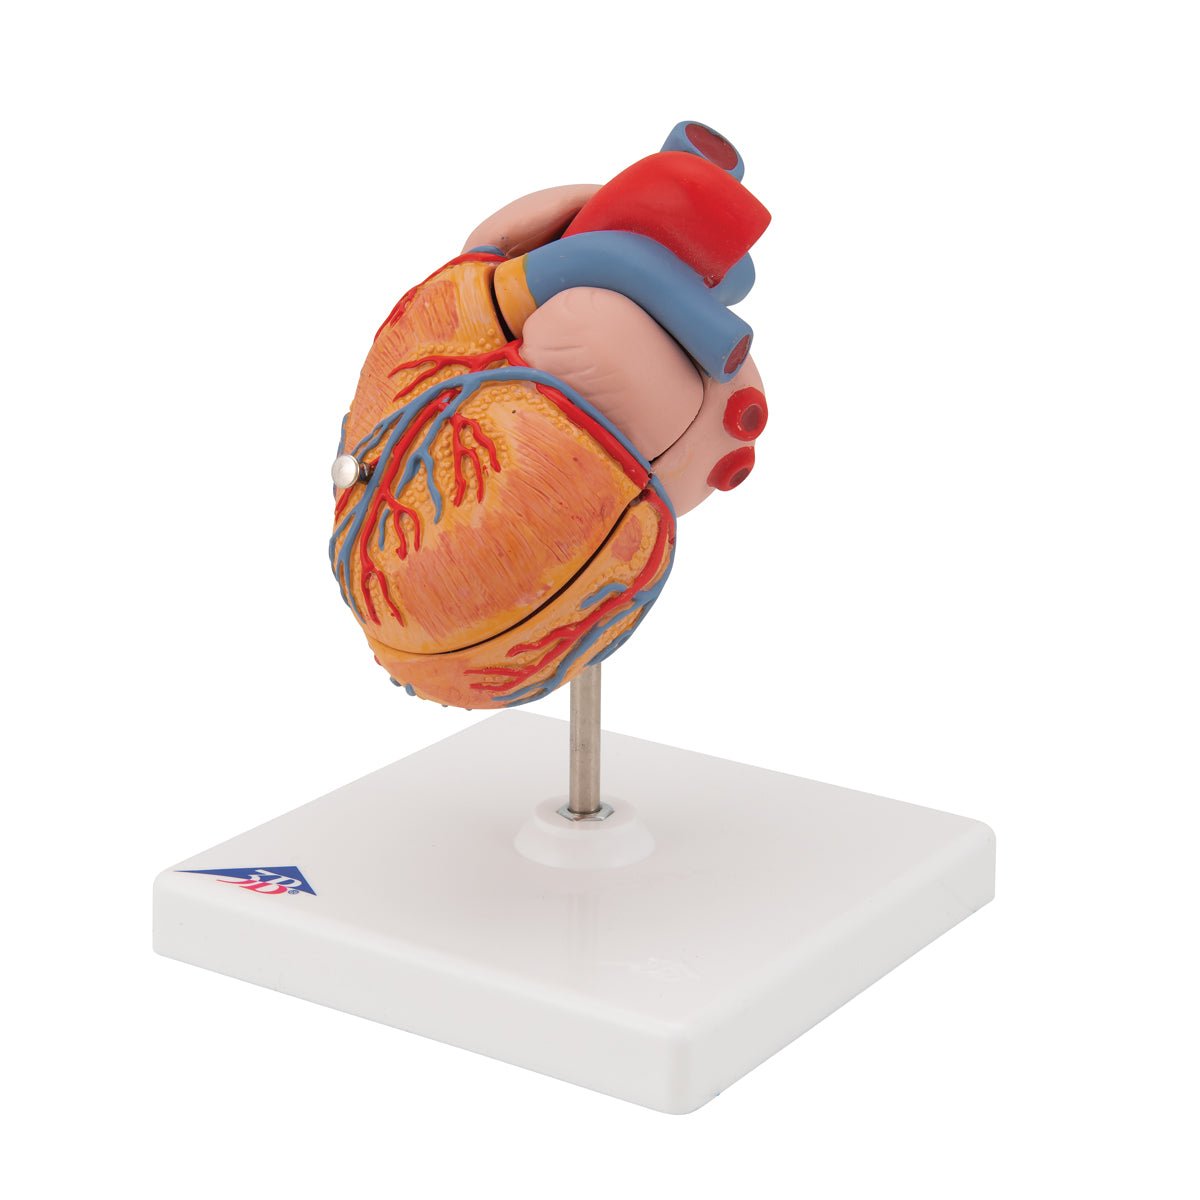

Selling anatomical models is the mainstay of eAnatomi, although we also spend a lot of resources developing our own anatomical materials such as posters. Anatomical models are used for various purposes and can show both defined tissues, organs and organ systems. Are you looking for a simple model of bone tissue or perhaps an advanced torso model based on MRI technology, you can find it all at eanatomi.com.